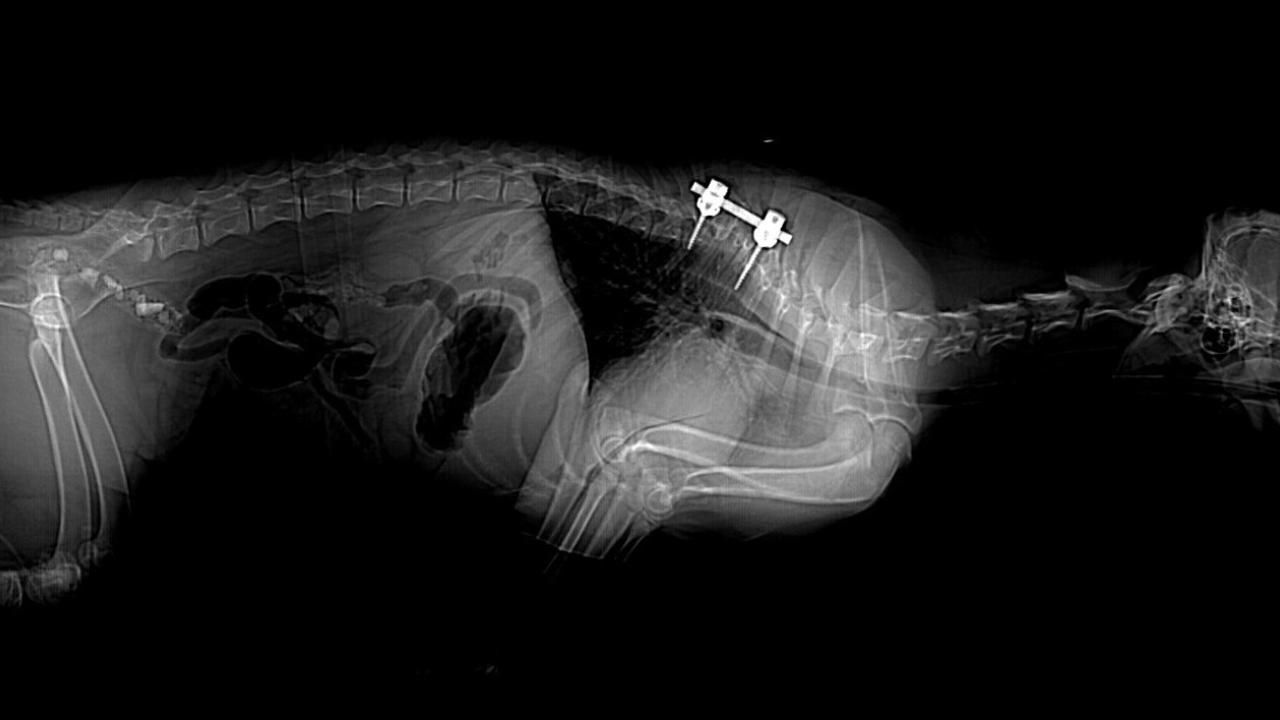

During her examination at the hospital, Kailana was able to walk independently, but presented with a uncoordinated hind end gait and reduced awareness of where her hind limbs were position in relation to her body.1 The team then brought in the Anesthesia and Diagnostic services to perform a CT, which showed multiple vertebral anomalies from her 4th thoracic vertebrae (T4) to her 9th thoracic vertebrae (T9) (most severe from T5 to T8). This caused marked spinal curvature and spinal cord compression at ^t to T7, and in narrowing of the spinal canal. After learning all of this information, the neurologists now believe her condition is more likely congenital rather than traumatic.1

When Kailana turned 6 months old, Lim proceeded with the surgery. The surgery was a 7-hour operation that involved a corpectomy at the site of the most severe spinal cord compression, which was then followed by stabilization of the spin using pedicle screws and rod. According to the organizational release, corpectomy for congenital vertebral malformations is an especially demanding procedure. The spinal cord is extremely thin at the stenotic site and the bone requiring removal is very close to the this fragile tissue. One small error could cause severe spinal cord damage and paralysis.